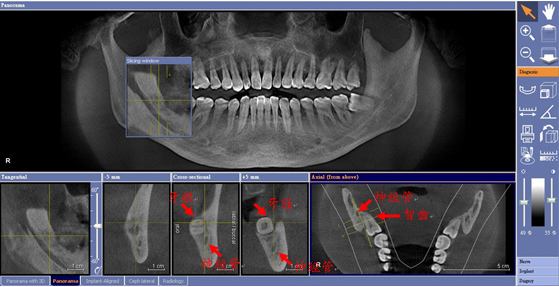

3、拔智齒難度:智齒的具體生長情況決定了拔牙的價格上的差異,在拔智齒前醫(yī)生會進行全面的檢查,如果智齒出現(xiàn)橫著長或者靠近牙神經(jīng)的話,則難度會較高,一般人只需拍個口腔全景片,但相對于智齒靠近神經(jīng)管的情況,還可能需要拍CT,因此,費用也相對的較高。